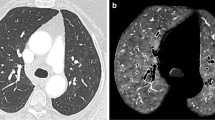

DECT angiography identified overt PE in only two patients (6.5%). In the lung perfusion maps, these patients had PDs corresponding to the areas with vascular occlusion and areas of decreased perfusion without visible thrombus (Fig. 1). Apart from these two cases, PDs were visualized in six more patients who had no detectable emboli in the pulmonary arteries (Fig. 2). In total, there were 8 patients with PDs and 2 patients among them had gross filling defects in the pulmonary arteries. The PDs did not overlap with GGOs or consolidation. In the subgroup analysis, patients with PDs had prolonged hospital stays (12.28 ± 8.81 vs 6.83 ± 5.04 days, p = 0.138), higher rates of ICU admission (37.5% vs 4.3%, p = 0.043), higher CT scores (13.3 ± 8.2 vs 5 ± 5.4, p = 0.025), and a more severe (type 3) disease (50% vs 4.3%, p = 0.010). The only significantly frequent clinical symptom in the patients with PDs was sore throat (50% versus 13%, p = 0.031). BMI was higher in patients with PDs (28.85 ± 3.77 vs 25.94 ± 3.12 kg/m2, p = 0.040). Smoking status was similar in the two groups (25% vs 26%, p = 0.952) (Table 1). Ferritin, AST, fibrinogen, D-dimer, CRP, and troponin plasma levels were significantly higher, and albumin levels were significantly lower in patients with PDs (Table 2). A receiver operator characteristic (ROC) curve analysis revealed that D-dimer plasma levels ≥ 0.485 μg/L predicted lung PD with 100% specificity and 87% sensitivity (area under the (AU)ROC, 0.957) and with a positive predictive value of 80% and a negative predictive value of 100% (Fig. 3). When we grouped patients according to the extent of PDs, there were statistically significant differences in terms of clinical classification, CT score, presenting symptoms like sore throat, and the need for oxygen therapy (Table 3). D-dimer was the only laboratory variable related to PD (p = 0.01).

A 36-year-old female with coronavirus disease 2019 (COVID 19). No evidence of a PE can be seen on contrast-enhanced dual-energy computed tomography (DECT) angiography (a and b). On the perfusion map images (c), perfusion deficits (arrowheads) can be seen in both lungs. On the coronal renal perfusion images (d), heterogeneous kidney enhancement with perfusion deficits (arrows) can be seen